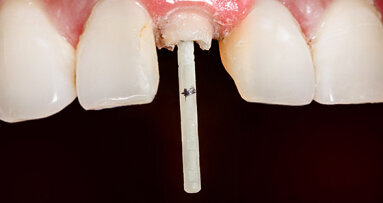

The suggested solution to the high polymerization and contraction stress caused by bulk filling the access opening is to reduce the mass or bulk of composite by placing multiple Fiber Post Segments into the composite mass, before curing with the LED light. It has been conclusively shown that even when the C-Factor is at 200 or more in a prepared root canal, minimizing the thickness of the composite (the mass), results in less contraction stress (S-Factor) which increases the patency of the bond to the root canal walls decreasing microleakage. [40-43] Of course, the placement of inserts into composite is not a new idea. Glass ceramic inserts and beta quartz have been used to decrease composite volumeand later silica glass and ceramics were introduced as a method for post-composite insertion bulk reduction. [44-46] These techniques demonstrated increased marginal patency and less microleakage, but the inserts were difficult to contour and polish with adhesion between the inserts and the composite being a challenge. [47,48] Composite megafillers were introduced later, as these were essentially the same as the matrix of the bulk filled composite, eliminating the inherent chemical differences between the materials. [49,50] The authors suggest the insertion of multiple high quality, high capacity, light conducting fibre post segments (not all fibre posts conduct light efficiently [51,52]). This is not only to reduce the composite volume, thereby minimizing the potential for microleakage, but is also equally as critical to use the light conductance of the fibre post segments to significantly increase the degree of polymerization of the dual-cure composite resin cements/core materials deep in the access opening, thereby increasing their physical properties. [53]

Due to the minimal invasiveness of the restoration, it is anticipated that after endodontic treatment, there would be enough coronal tooth structure left to allow for the preparation of a full coverage restoration with a fully circumferential ferrule of at least 2+mm in height, as well as width (Fig. 4). Figure 5 is a magnified view of the distal vertical crack, with the wear facet on the lingual cusp indicating a working side contact interference. Endo dontic therapy was initiated under the microscope and after a thorough debridement and shaping of the root canal spaces (Fig. 6), the roots were obturated with gutta percha using a continuous wave of condensation technique to a level 2mm below the pulpal floor (Fig. 7). Phosphoric acid etching was initiated with the placement of Ultra-Etch Etchant (Ultradent) followed by microbrush agitation to work the etchant into the dentine, a thorough rinse, and light air drying (Fig. 8). Figure 9 shows the application of MPa bonding agent (Clinical Research Dental) with a microbrush, which again was followed by agitation to facilitate deeper penetration of the bonding agent, followed by evaporation of the solvent for ten seconds. The bonding agent was cured with a Valo Curing Light (Ultradent) for ten seconds utilising a Valo Proxiball Lens (Fig. 10). The Macro-Lock X-RO segments are verified for fit over the three canal orifices, and then coated with MPa bonding agent, which was cured for ten seconds (Fig. 11). Cosmecore (Cosmedent) A2 is injected into the pulp chamber one half way up the occlusal height of the clinical crown (Fig. 12). The Macro-Lock X-RO segments are inserted into the Cosmecore followed by a 10 second cure with the Valo (Fig. 13). The rest of the occlusal access opening is filled with the Cosmecore and thoroughly cured with the Valo for 20 seconds. Figure 14 is the final post-operative radio graph showing the placement of the fibre segments into the core. The final restoration of the occlusal access opening is shown in Figure 15 after trimming and occlusal adjustment. The endodontically treated tooth is now ready for a final restoration.